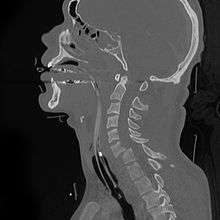

A fracture of the base of the dens (a part of C2) as seen on CT. | |